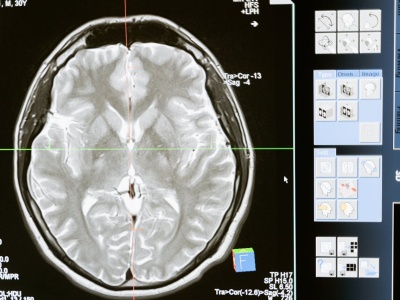

Bezpłatne badania nowotworów głowy i szyi w WCO. Sprawdź objawy, grupy ryzyka i dowiedz się, jak się zapisać. Artykuł Bezpłatne badania wykrywające nowotwory głowy i szyi w Poznaniu. Kto może skorzystać? pochodzi z serwisu Alert Medyczny.

Obrzęk, guzek – który nie boli. Najczęściej umiejscowione z boku twarzy, w okolicach ucha lub kości żuchwy. Zwłaszcza w sezonie infekcyjnym – uważamy, że to pozostałość po przeziębieniu, a w upalny dzień - to wina klimatyzacji. Wytłumaczeń jest wiele...